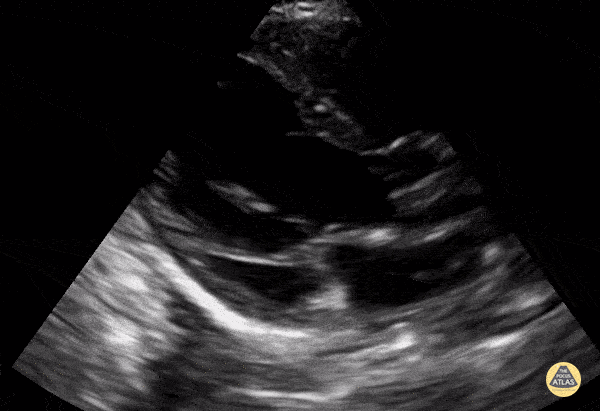

Normal PSLA in a 4-year-old preschooler. Contributor: Jaron Smith, MD, Phoenix Children's Hospital

View: Unspecified Parasternal Long Axis Parasternal Short Axis Apical Four-Chamber Subcostal Four-Chamber Subcostal Inferior Vena Cava Right Upper Quadrant Left Upper Quadrant Suprapubic Longitudinal Suprapubic Transverse Subxiphoid Anterior Thoracic Phrenic